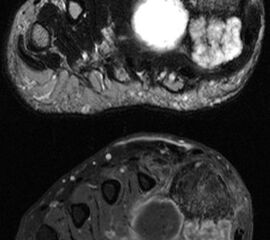

Benigne Weichteiltumoren

Stellvertretend für gutartige tumoröse Weichteilgeschwulste soll hier die pigmentierte villo-noduläre Synovialitis (PVNS) als wohl häufigste gutartige Weichteilneoplasie des Fußes erörtert werden. Die PVNS nimmt als einzige Entität in allen größeren Studien zu Fußtumoren einen der drei vorderen Plätze ein. Als Synonym der extra-artikulären Form der PVNS ist der Begriff des teno-synovialen Riesenzelltumors gebräuchlich. Die sehnenscheiden- und gelenkkapselreiche Fußanatomie prädestiniert für die Entstehung einer PVNS (Abb. 32). Das weibliche Geschlecht ist doppelt so häufig betroffen, das bevorzugte Alter liegt zwischen 30-50 Jahren. Eine schmerzlose, nur langsam größenprogrediente Schwellung ist das häufigste Symptom. Die Rezidivrate wird mit bis zu 30% angegeben 49. Bei der PVNS handelt sich um einen fibro-histiozytären Tumor (echte Neoplasie) und nicht wie ehemals angenommen um ein inflammatorisches oder posttraumatische Geschehen. Für die intraartikuläre Form, die wiederum in eine noduläre/lokalisierte und diffuse Form unterteilt werden kann, stellt das Sprunggelenk die dritt-häufigste Lokalisation am gesamten Körper dar (Abb. 33).

Im Röntgen zeigt sich gelegentlich eine gut abgrenzbare Weichteilformation (bei nodulärer Form) und knöcherne Druckarrosionen der angrenzenden Knochen. Sekundäre arthrotische Veränderungen der angrenzenden Gelenke sind möglich. Die MRT kann mit einem stark T2-gewichtetem Gradientenecho sog. Suszeptibilitätsartefakte der Hemosiderin­ablagerungen darstellen. Diese führen gewöhnlich zu charakteristischen Signalaus­löschungen in T1 und T2 gewichteten Sequenzen. Eine Kontrastmittel-Aufnahme erfolgt in der Regel diffus und inhomogen. Die Therapie besteht in einer offenen Resektion. Wir raten dringend davon ab, intraartikuläre, lokalisierte Formen der PVNS per Arthroskopie resezieren zu wollen. Dieser Tumor sollte, wenn möglich, marginal und nicht intraläsional reseziert werden. Eine arthroskopische Zerkleinerung mit dem Shaver würde aus einer nodulären Form eine diffuse Form produzieren und die Rezidivwahrscheinlichkeit deutlich steigern. Ebenso ist vor einer Radiosynoviorthese (RSO) bei Vorliegen einer nodulären Variante abzuraten. Bei diesem nuklearmedizinischen Verfahren, welches gewöhnlich Anwendung bei chronisch entzündlichen Gelenkerkrankungen findet, werden Beta-Strahler in Gelenke injiziert. Ein therapeutischer Effekt hat sich bisher nicht nachweisen lassen.